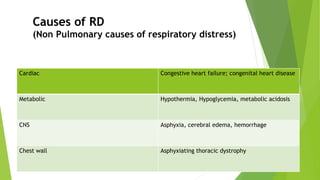

This document discusses respiratory distress and respiratory distress syndrome in neonates. It defines respiratory distress and describes the clinical signs. Various pulmonary and non-pulmonary causes are outlined. Respiratory distress syndrome, also known as hyaline membrane disease, is described in detail, including risk factors, pathophysiology, clinical presentation, investigations, complications, prevention, and treatment approaches like surfactant administration and nasal continuous positive airway pressure. The prognosis depends on gestational age and quality of care provided.